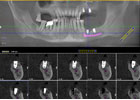

5顆釘種出半口牙,古稀老人種牙當天用!